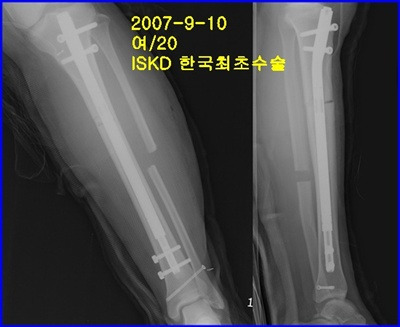

종아리 뼈(경골) 연장 - 국내최초 ISKD